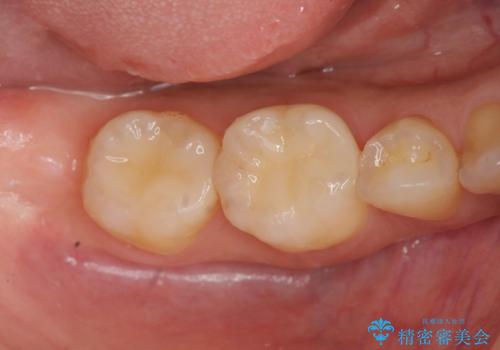

口の中の金属を外したい セラミッククラウンによる治療

- 笑った時に口の中で目立つ金属を外したい、虫歯の治療を再発の内容しっかりと行って欲しいと希望され来院されました。

銀歯・虫歯を丁寧に除去したのち精密なセラミック治療を行うことで長期的な予後を目指します。

- 57万円(仮歯・ファイバーコア・ジルコニアクラウン×5)費用は治療当時の料金となります

銀歯をを外すだけでなく、セラミックを適合よく精密に製作することで長期的な予後を見込むことが可能になります。